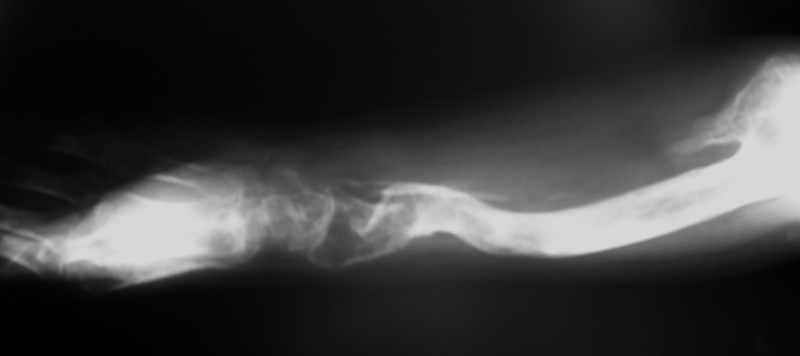

Ещё одно клиническое наблюдение - лимфома кости, до и после ПХТ и лучевой терапии.

Примите мои извенения, если я Вас чем-либо обидел. Никакого пренебрежения, просто хотел поделиться наблюдением, а главное, результатом консервативного (ПХТ и лучевая терапия) лечения.